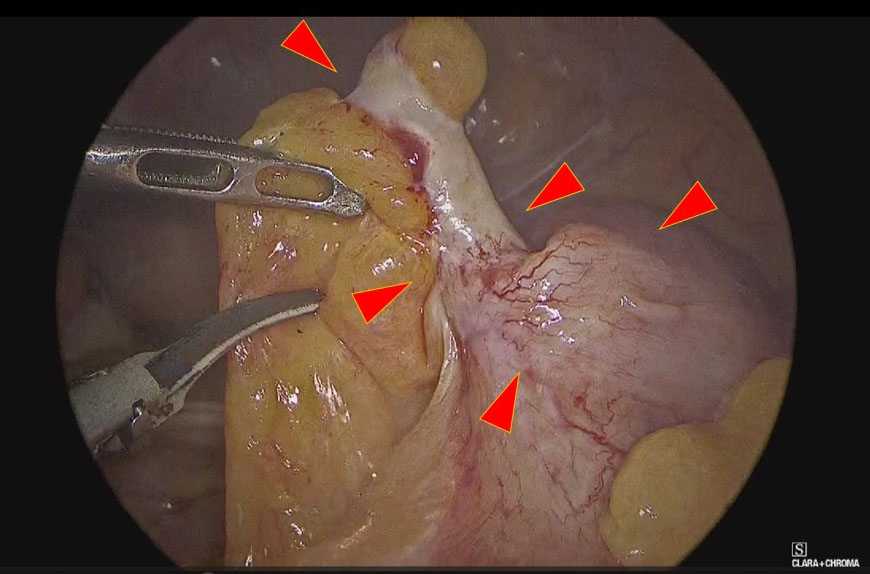

Figure 2

Figure 2. Intraoperatively, the appendix was infiltrative and indurated, similar to appendicitis.